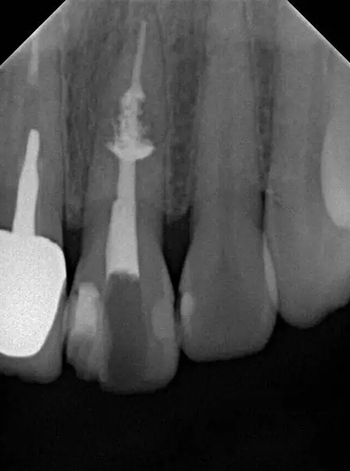

診斷:左上中切牙牙根內(nèi)吸收。治療計劃:左上中切牙根管治療,全冠修復(fù)。 治療過程:患者知情同意。使用含1/100,000腎上腺素的4%鹽酸阿替卡因(碧蘭麻,艾龍)局部浸潤麻醉,橡皮障隔濕。去腐未盡露髓,露髓孔出血多。開髓,使用10#不銹鋼K銼(MANI,日本)探查根管,根管中段有鈣化物阻擋,不能達到牙根全長(圖3A)。在顯微鏡下(Leica M400E,萊卡, 德國) 使用超聲尖(E1根管治療超聲尖,啄木鳥公司,中國)通開,采用根管長度測量儀(Root ZX, Morita公司,日本)加診斷絲片法(圖1B)測量根管長22 mm。使用控制扭矩馬達(X-smart,登士柏)和鎳鈦旋轉(zhuǎn)器械(Hero 642, Micromega)根管預(yù)備,根管預(yù)備過程中使用5.25%次氯酸鈉溶液沖洗。 根備完成后使用超聲蕩洗根管,5.25%次氯酸鈉溶液3 分鐘, 17% EDTA溶液1分鐘。干燥根管,使用螺旋充填器根管內(nèi)封氫氧化鈣糊,氧化鋅丁香油水門汀暫封。1周后患者復(fù)診,患者述無術(shù)后不適,檢查暫封完好,無叩痛,不松,牙齦無紅腫瘺管。使用橡皮障隔濕,去除暫封物,超聲蕩洗根管,5.25%次氯酸鈉溶液3 分鐘, 17% EDTA溶液1分鐘。干燥根管,牙膠尖(達雅鼎,中國)和必蘭根充糊劑(Cortisomol, 艾龍公司,法國)熱垂直加壓法根管充填。術(shù)后片顯示根充恰填,可見牙膠/糊劑被壓入鈣化物周圍和內(nèi)部縫隙內(nèi)

1月后復(fù)查無不適,行全瓷冠修復(fù)。8月2周后復(fù)查,患者無不適主訴,牙冠美觀,邊緣完好,患牙無叩痛,不松動,牙齦無紅腫瘺管, X線片示根周膜連續(xù),根尖周未見異常。建議患者避免用前牙撕咬食物,定期復(fù)查。 討論: 臨床上,由于牙根內(nèi)吸收和牙根外吸收的治療方法和預(yù)后不同,常需要對兩者進行鑒別診斷。過去通常采用偏移投照的方法鑒別兩者。在偏移投照片上,外吸收病損和根管輪廓相對位置較正位片會發(fā)生變化,而內(nèi)吸收病損則不會[12]。